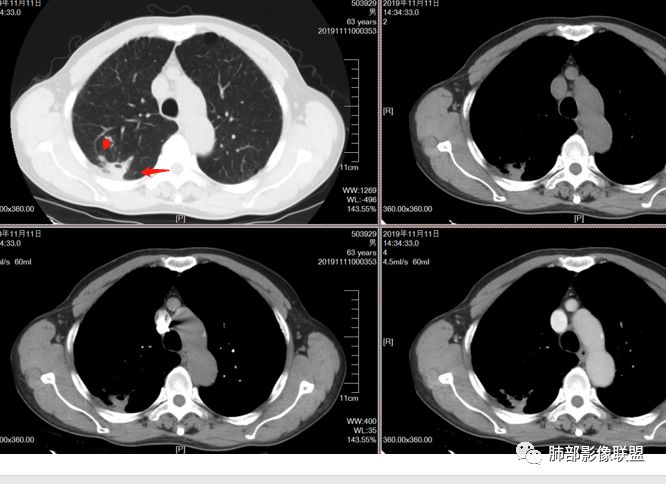

一米阳光:双肺胸膜下多发结节病影,小结节融合,病灶与胸膜面平行,垂直支气管,边缘模糊,晕征,支气管进入堵塞,内见小空洞,增强均匀强化。结合病史,有类风湿病史,考虑炎性肉芽肿,隐球菌感染。鉴别,结核建议,穿刺,隐球荚膜抗原检查

雪上一枝蒿(陈显静):右上肺病灶,似见周边卫星灶,空洞朝向肺门,考虑炎性病变,结核?左下肺结节长轴平行胸膜,强化后似有低密度影,隐球菌?二元论?。

破风5:胸部CT:右上叶胸膜下病变,与胸膜宽基底相连,累及胸膜,病灶内可见空洞,洞壁光滑,病灶周围有散在卫星灶。有类风湿激素口服历史,结核首先考虑。左肺下叶背段胸膜下实变,病灶边界清楚,与长轴与胸膜平行,血管伸入,纵隔窗可见糊墙征。考虑良性病变,隐球?总体,右上肺结核,左下肺隐球,CTD-ILD

流心明智:患者,老年男性,既往有类风湿关节炎,长期口服激素史。胸CT:间隔旁肺气肿,右肺上叶后段胸膜下病变,与胸膜宽基底相连,局部胸膜增厚,病灶内向肺门侧空洞,病灶周围卫星灶。考虑炎性病灶。左肺下叶胸膜下气肿背景边缘实变、边界清楚、有膨隆、滋养血管征,软毛刺、多结节融合、糊墙征。 总体考虑:良性病变,右上:结核?左下:隐球菌?左下鉴别Ca。

南边:糊墙,长轴与胸膜平行;边缘收缩+膨隆;脐凹征

脐凹征,高度提示恶性

因为其与胸膜的关系与右上叶的不一致,所以不能一元论

而且周围的表现不一致

还有就是间质性病变基础上,恶性变的几率很高